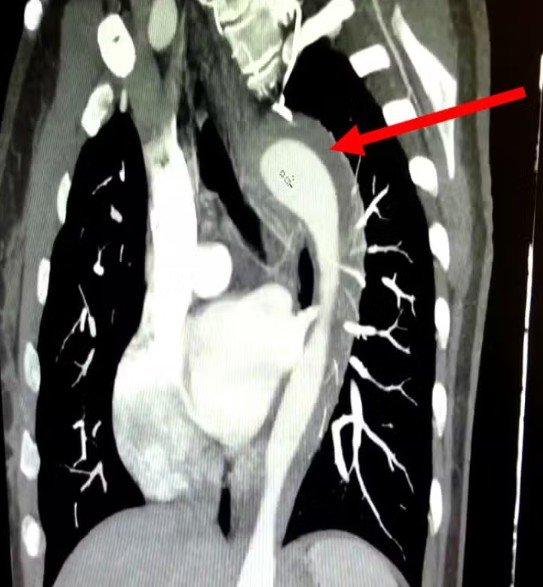

A investigação médica revelou que a paciente possuía um histórico de hipertensão não tratada por um ano e era tabagista crônica há 17 anos. Esses fatores de risco foram cruciais para o desenvolvimento de um hematoma intramural na aorta, uma condição séria caracterizada por sangramento dentro da parede da maior artéria do corpo.

Classificada como uma Síndrome Aórtica Aguda (SAA), essa condição é extremamente perigosa e, se não for diagnosticada e tratada rapidamente, pode progredir para complicações fatais como aneurisma ou ruptura completa da aorta, com uma taxa de mortalidade que aumenta drasticamente a cada hora sem intervenção.

O tratamento para o hematoma intramural na aorta varia conforme a localização e a extensão da lesão, podendo ser clínico ou cirúrgico. No caso em questão, a paciente recebeu medicação e foi prontamente encaminhada para uma cirurgia cardiotorácica, procedimento que se mostrou vital para sua recuperação. Graças à intervenção rápida e eficaz, a mulher teve alta hospitalar em apenas três dias.